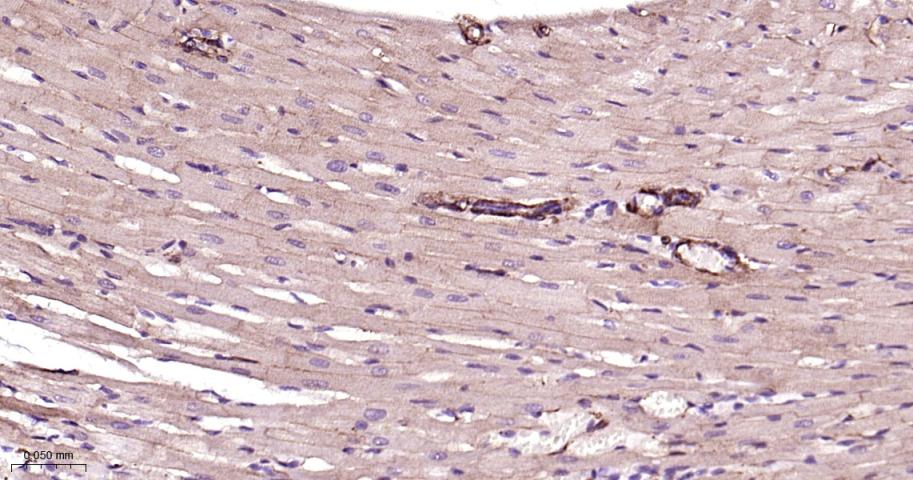

Paraformaldehyde-fixed, paraffin embedded Rat Heart; Antigen retrieval by boiling in sodium citrate buffer (pH6.0) for 15 min; Antibody incubation with Vinculin Monoclonal Antibody, Unconjugated(bsm-54148R) at 1:200 overnight at 4°C, followed by conjugation to the bs-0295G-HRP and DAB (C-0010) staining.

Paraformaldehyde-fixed, paraffin embedded Mouse Heart; Antigen retrieval by boiling in sodium citrate buffer (pH6.0) for 15 min; Antibody incubation with Vinculin Monoclonal Antibody, Unconjugated(bsm-54148R) at 1:200 overnight at 4°C, followed by conjugation to the bs-0295G-HRP and DAB (C-0010) staining.